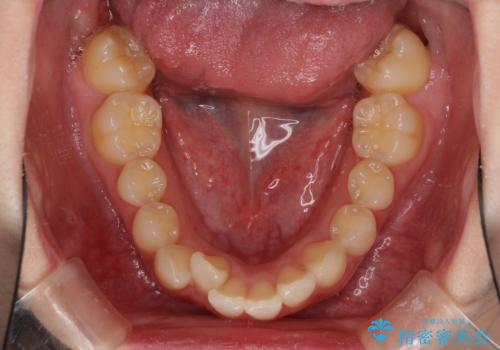

左右ともに上顎奥歯が外を向き、下顎奥歯が内側に倒れているシザーズバイトであったため、補助装置により改善することとしました。

上下の咬み合わせは、下顎に対して上顎が相対的に前方にあったため、奥歯のシザーズバイト改善後に上顎左右第一小臼歯2本を抜歯し、上顎前突を改善していくこととしました。